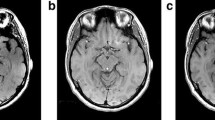

Case 2 (DLB)

NmMRI of the midbrain showed that the signal intensity of the SNc was the same as that of the SC. Mild hyperintensity in the left lateral part of the SNc was seen. Mild increased signal intensity was also seen in the left lateral part of the cerebral peduncle (Fig. 3a). Myelin staining of the SNc was the same as that of the SC, whereas strong myelin staining was seen in the red nucleus, medial lemniscus, and cerebral peduncle (Fig. 3b). Diffuse ferritin deposition in the SNc was milder than that in the red nucleus, medial lemniscus, and cerebral peduncle (Fig. 3c). Histologically, the signal intensity of the SNc was the same as the intensity of the SC, reflecting severe loss of neuromelanin-containing neurons, fine bundles of myelinated nerve fibers, and dilated perivascular spaces (Fig. 3d–f).

Case 2 (DLB case). a NmMRI of the midbrain shows no apparent hyperintense area in the SNc. The signal intensity in the SNc is the same as that of the SC. Mild hyperintensity in the left lateral part of the SNc is seen. Mild increased signal intensity is also seen in the left lateral part of the cerebral peduncle. b A myelin-stained (Klüver–Barrera stain) section corresponding to a shows that staining of the SNc is the same as that of the SC. Strong myelin staining is seen in the red nucleus, medial lemniscus, and cerebral peduncle. c Ferritin immunohistochemistry corresponding to a shows that ferritin deposition in the SNc is milder than that in the red nucleus, medial lemniscus, and cerebral peduncle. d NmMRI of the SNc (boxed area in a) shows mild hyperintensity in the lateral part of the SNc. e A myelin-stained (Klüver–Barrera stain) section corresponding to the boxed area in b. f Histological finding of the boxed area in e shows severe loss of neuromelanin-containing neurons. Fine bundles of myelinated nerve fibers (black arrows) and dilated perivascular spaces (white arrows) are seen in the SNc

Case 3 (PD)

NmMRI of the midbrain showed that the signal intensity in the SNc was the same as that of the SC (Fig. 4a). Myelin staining of the SNc was the same as that of the SC, whereas strong myelin staining was seen in the red nucleus, medial lemniscus, and cerebral peduncle (Fig. 4b). Diffuse ferritin deposition in the SNc was milder than that in the red nucleus, medial lemniscus, and cerebral peduncle (Fig. 4c). Histologically, the signal intensity of the SNc was the same as the intensity of the SC, reflecting severe loss of neuromelanin-containing neurons, fine bundles of myelinated nerve fibers, and dilated perivascular spaces (Fig. 4d–f).

Case 3 (PD case). a NmMRI of the midbrain shows no apparent hyperintense area in the SNc. The signal intensity of the SNc is the same as that of the SC. Nonhomogenous hyperintensity due to artifact is seen in the right lateral part of the SNc. b A myelin-stained (Klüver–Barrera stain) section corresponding to a shows that staining of the SNc is the same as that of the SC. Strong myelin staining is seen in the red nucleus, medial lemniscus, and cerebral peduncle. c Ferritin immunohistochemistry corresponding to a shows that ferritin deposition in the SNc is milder than that in the red nucleus, medial lemniscus, and cerebral peduncle. d NmMRI of the SNc (boxed area in a) shows no apparent hyperintense area in the SNc. e A myelin-stained (Klüver–Barrera stain) section corresponding to the boxed area in b. f Histological finding of the boxed area in e shows severe loss of neuromelanin-containing neurons. Dilated perivascular spaces (white arrows) are seen in the SNc